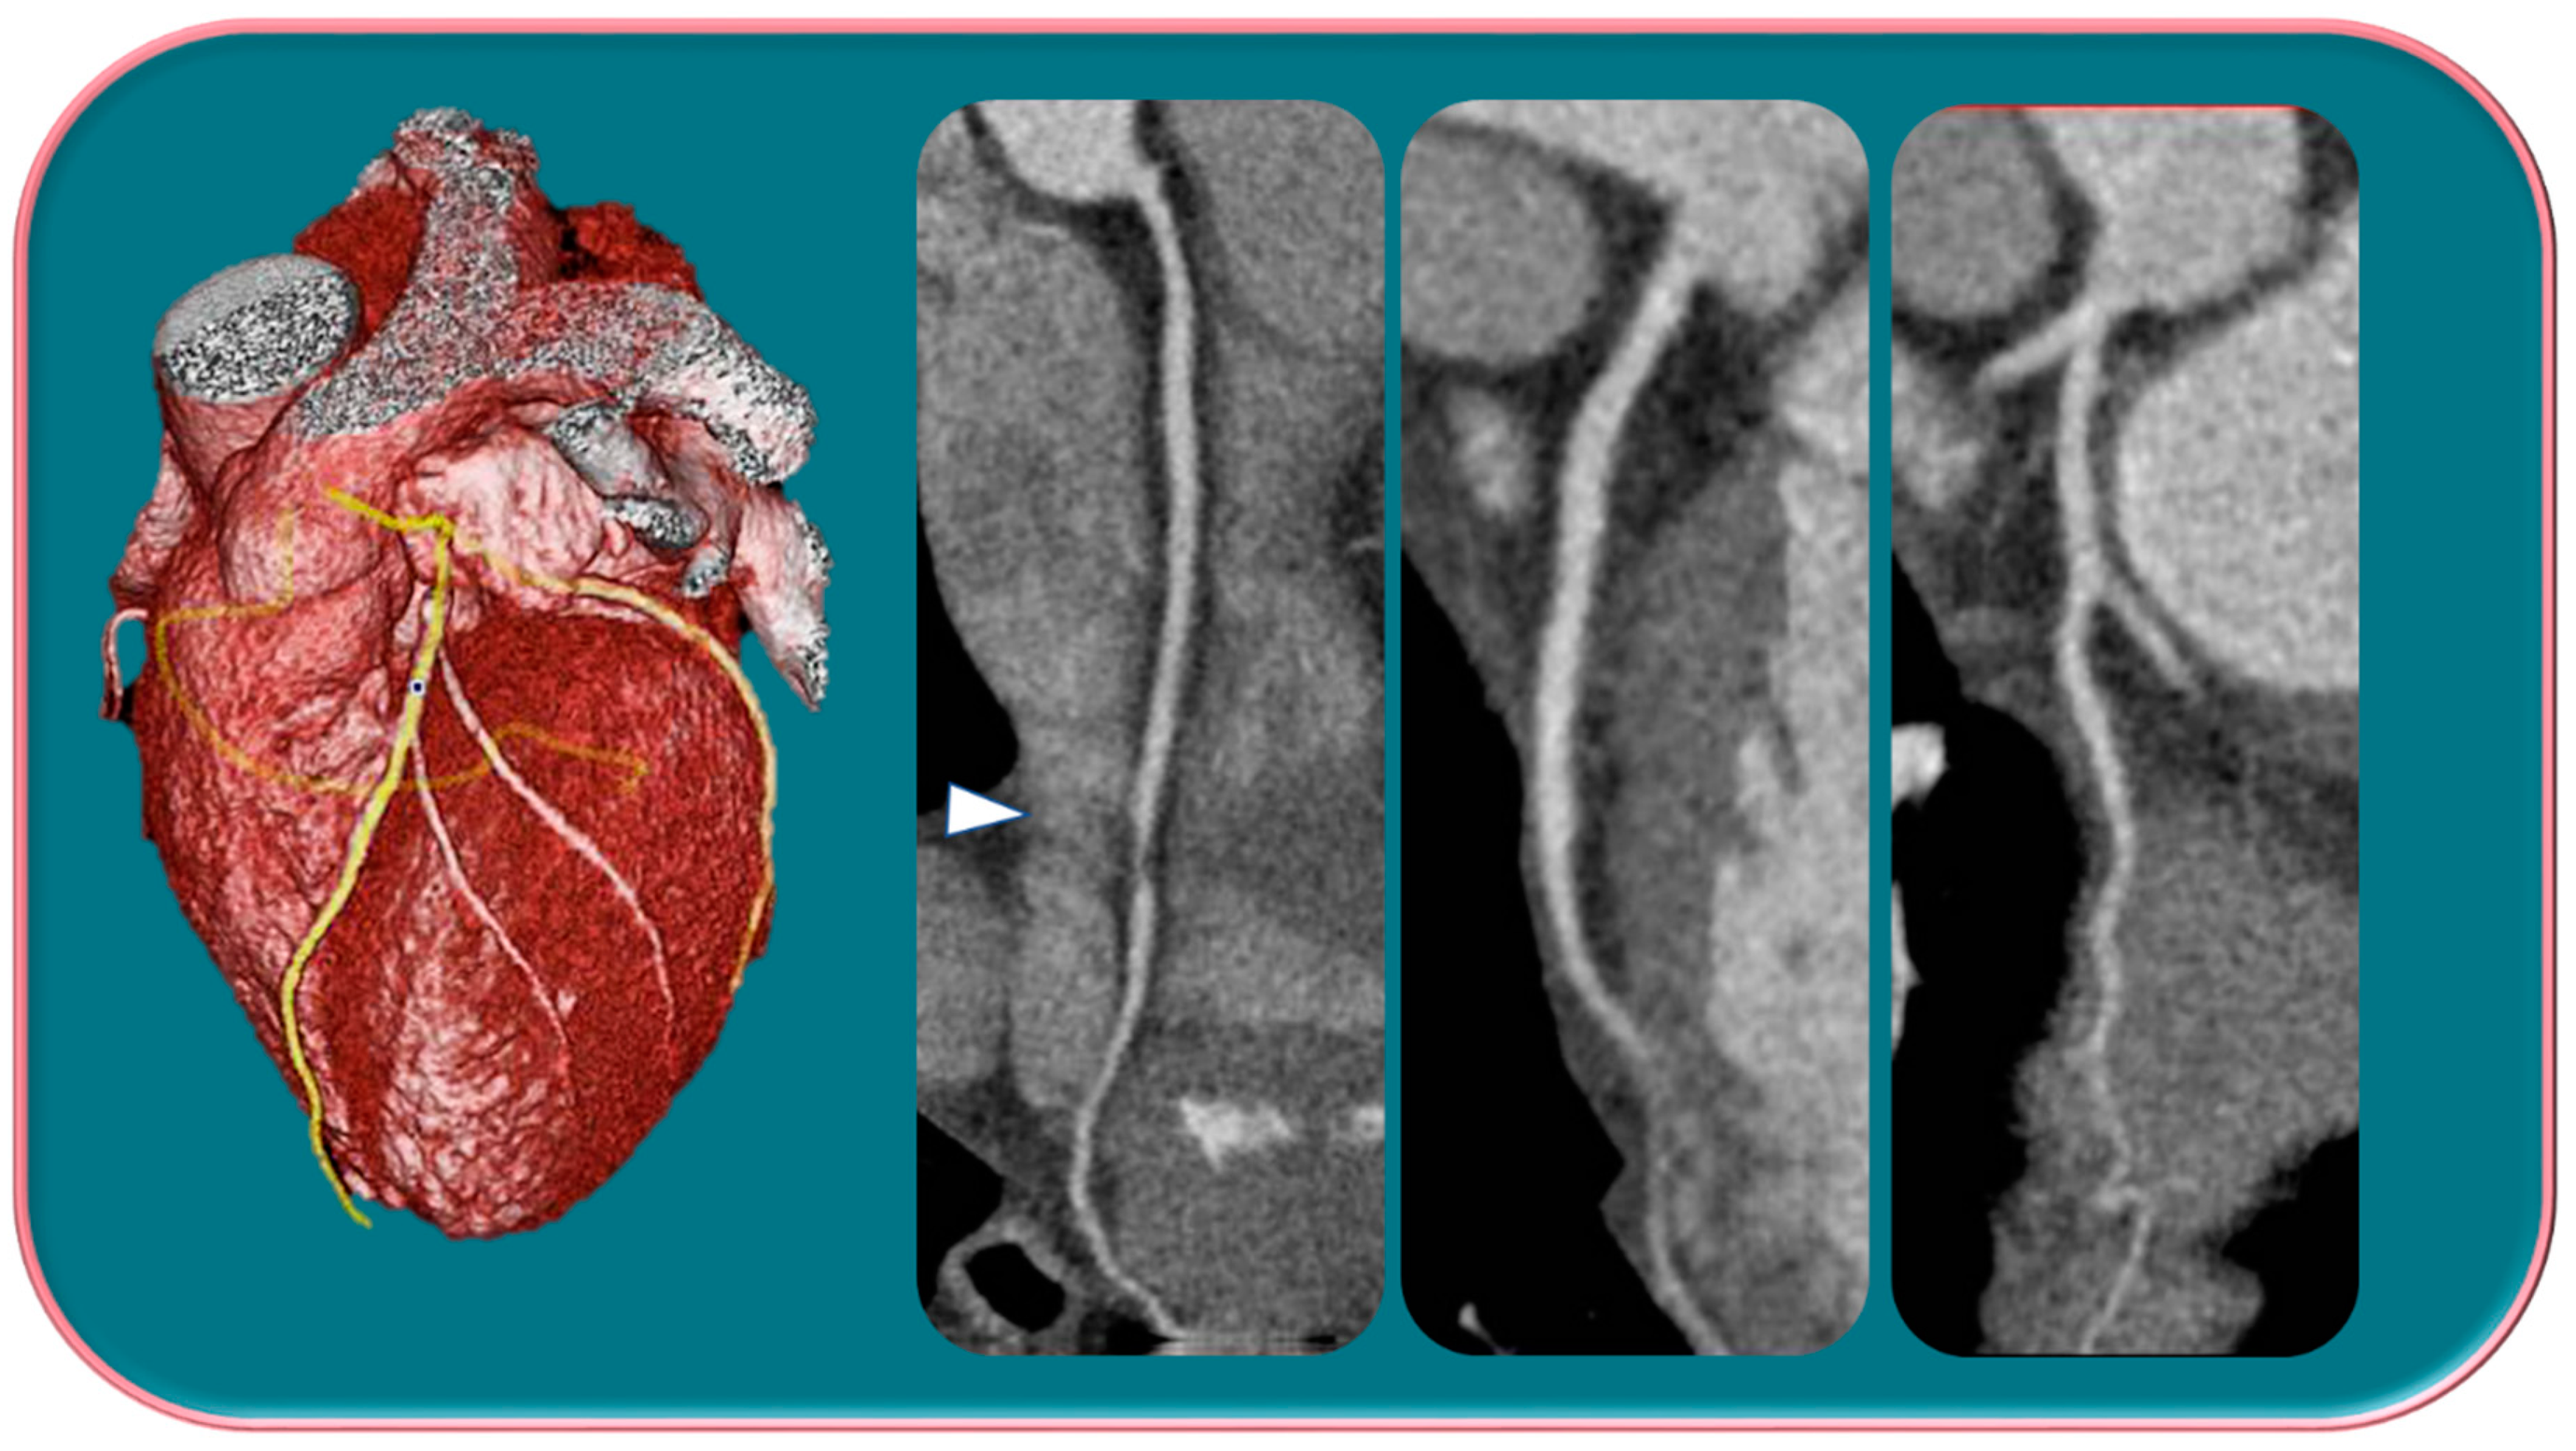

Similarly, an increase in exogenous estrogen exposure, such as the estrogen treatment of prostate cancer and transgender hormone therapy, is responsible for an increase in risk of male BC (Figure 8) [158].

Figure 8.

Man with retroareolar tumor and skin thickening.

Endogenous causes of hyperoestrogenization in men, including obesity, cirrhosis, mumps orchitis, or testicular lesions, have also been associated with an increased risk of MBC.